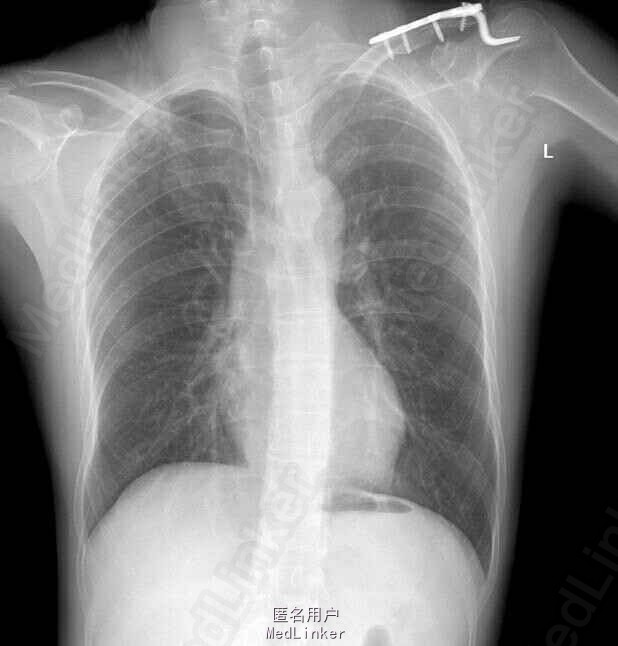

正常左肩锁骨x光图片,正常锁骨ct图

左锁骨骨折

锁骨骨折(a):注意描述骨折部位(近,中,远段);肩胛骨骨折(b).